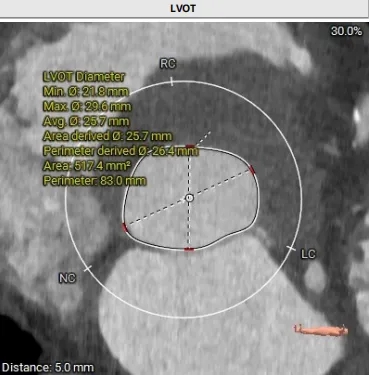

主动脉根部测量

周长74.4 周长径23.7

周长83 周长径26.4

周长77.3 周长径24.6

周长82.8 周长径26.4

周长92.8 周长径29.5

周长98.2 周长径31.3